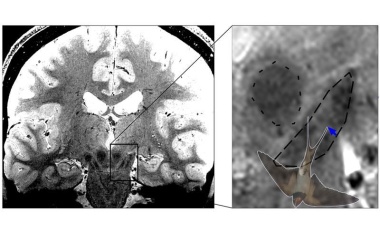

Neurophysiker um Malte Brammerloh vom MPI CBS haben herausgefunden, dass die Identifikation von einem Magnetresonanztomographie-Zeichen zur Parkinsondiagnose als eine bestimmte anatomische Region im Gehirn zwar weit verbreitet, aber gar nicht korrekt ist.